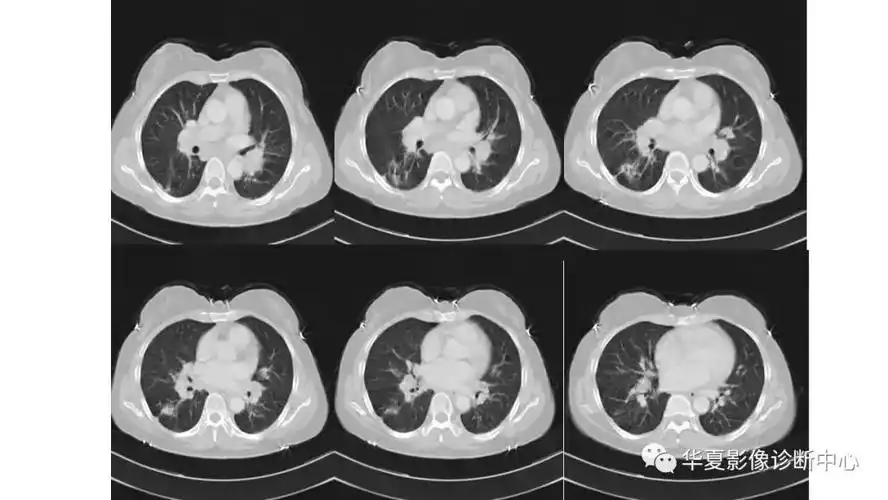

会移动的肺结节.左肺上叶前段胸膜下肺混合型结节,仰卧位扫描( - 抖音

多发肺结节之肺隐球菌病丨小打卡读片精选36